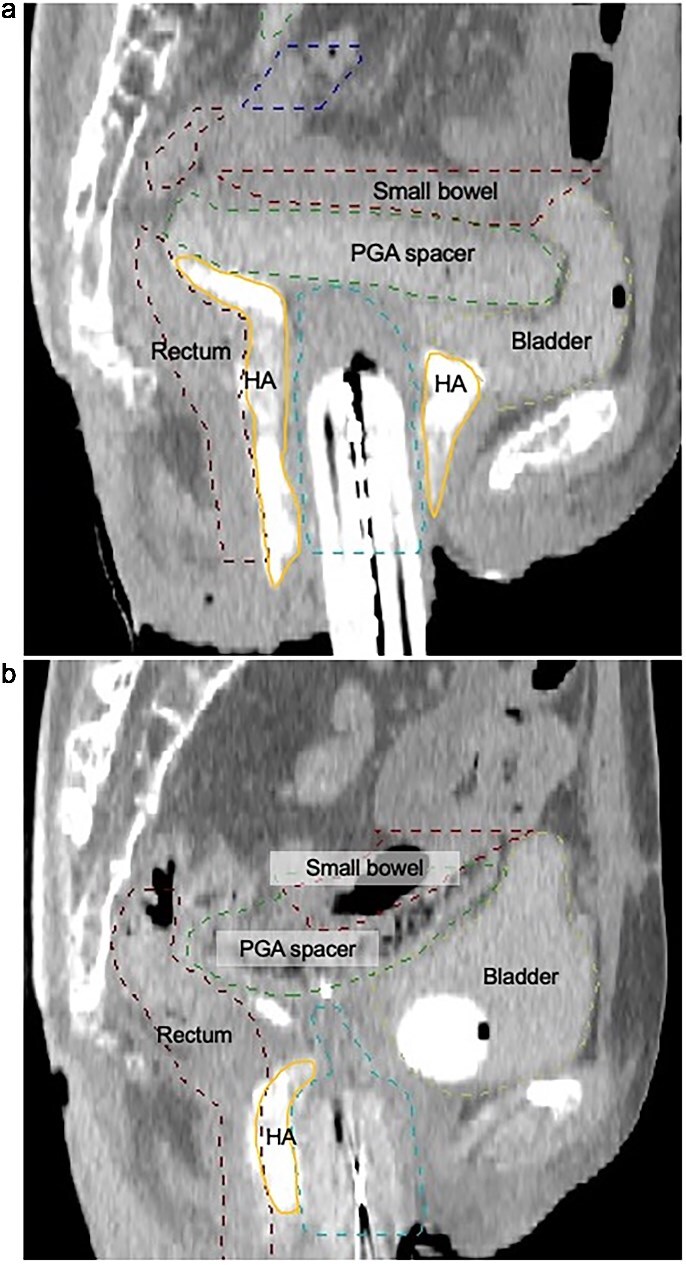

In recurrent gynecologic malignancies following prior pelvic irradiation, definitive radiation therapy is often precluded by cumulative dose constraints to adjacent organs at risk (OARs), and patients may be left with only highly invasive surgical options such as total pelvic exenteration. While some institutions have explored displacement techniques such as artificial ascites or hyaluronic acid gel injection, these approaches are not widely adopted and frequently fail to ensure consistent and stable separation of OARs. We report the first clinical use of Neskeep®, a bioabsorbable polyglycolic acid (PGA) spacer, in high-dose-rate (HDR) brachytherapy for recurrent cervical cancer after prior pelvic radiation. A woman in her 40s with prior hysterectomy and HDR brachytherapy for cervical intraepithelial neoplasia grade III developed vaginal stump recurrence 4 years later. Laparoscopic placement of the PGA spacer was performed to achieve durable displacement of the small bowel, followed by eight fractions of HDR brachytherapy. Hyaluronic acid gel was also injected during each fraction to displace the bladder and rectum. The spacer maintained position and volume throughout treatment without complications. Dose-volume analysis showed a marked reduction in small bowel D₂cc (mean equivalent dose in 2 Gy fractions (EQD₂): 121.6 cGy) compared to the initial treatment (606.0 cGy), while the spacer itself received a mean D₂cc of 690.3 cGy. MRI confirmed complete response at 2 months, with no adverse events observed at that time point. The PGA spacer enabled safe, curative reirradiation in a case that would otherwise be unsuitable for further radiation therapy.